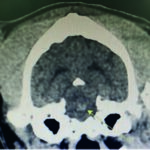

CT scan of skull is preferred for evaluate bone fractures and identify areas of acute hemorrhage or edema. CT scan showed multiple sites of skull fractures, right maxilla, both frontal, right zygomatic, right caudal mandible, right caudal zygomatic, right temporal, left occipital bone (Figure 3) and patchy small area of hyper-attenuation at the cranial of midbrain in pre-contrast study (Figure 4), no detectable mass effect, hypo-attenuated of large edematous parenchyma in the brain, right temporomandibular joint is displacement (Figure 5) and left tympanic bulla shows partial ventral fluid-filled.

Figures 4.1, 4.2

Patchy small area of hyper-attenuation at the cranial of midbrain in pre-contrast study.